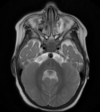

Q

35 anos, Masculino

A

Craniofaringioma adamantinomatoso

26

Criança

Craniofaringioma adamantinomatoso Crianças Lesão suprasselar com componente sólido e cístico; lobulado; calcificação anelar ou nodular presente em quase TODOS os craniofaringeomas pediátricos; Componente cístico proeminente e componente sólido pequeno, mas com realce.